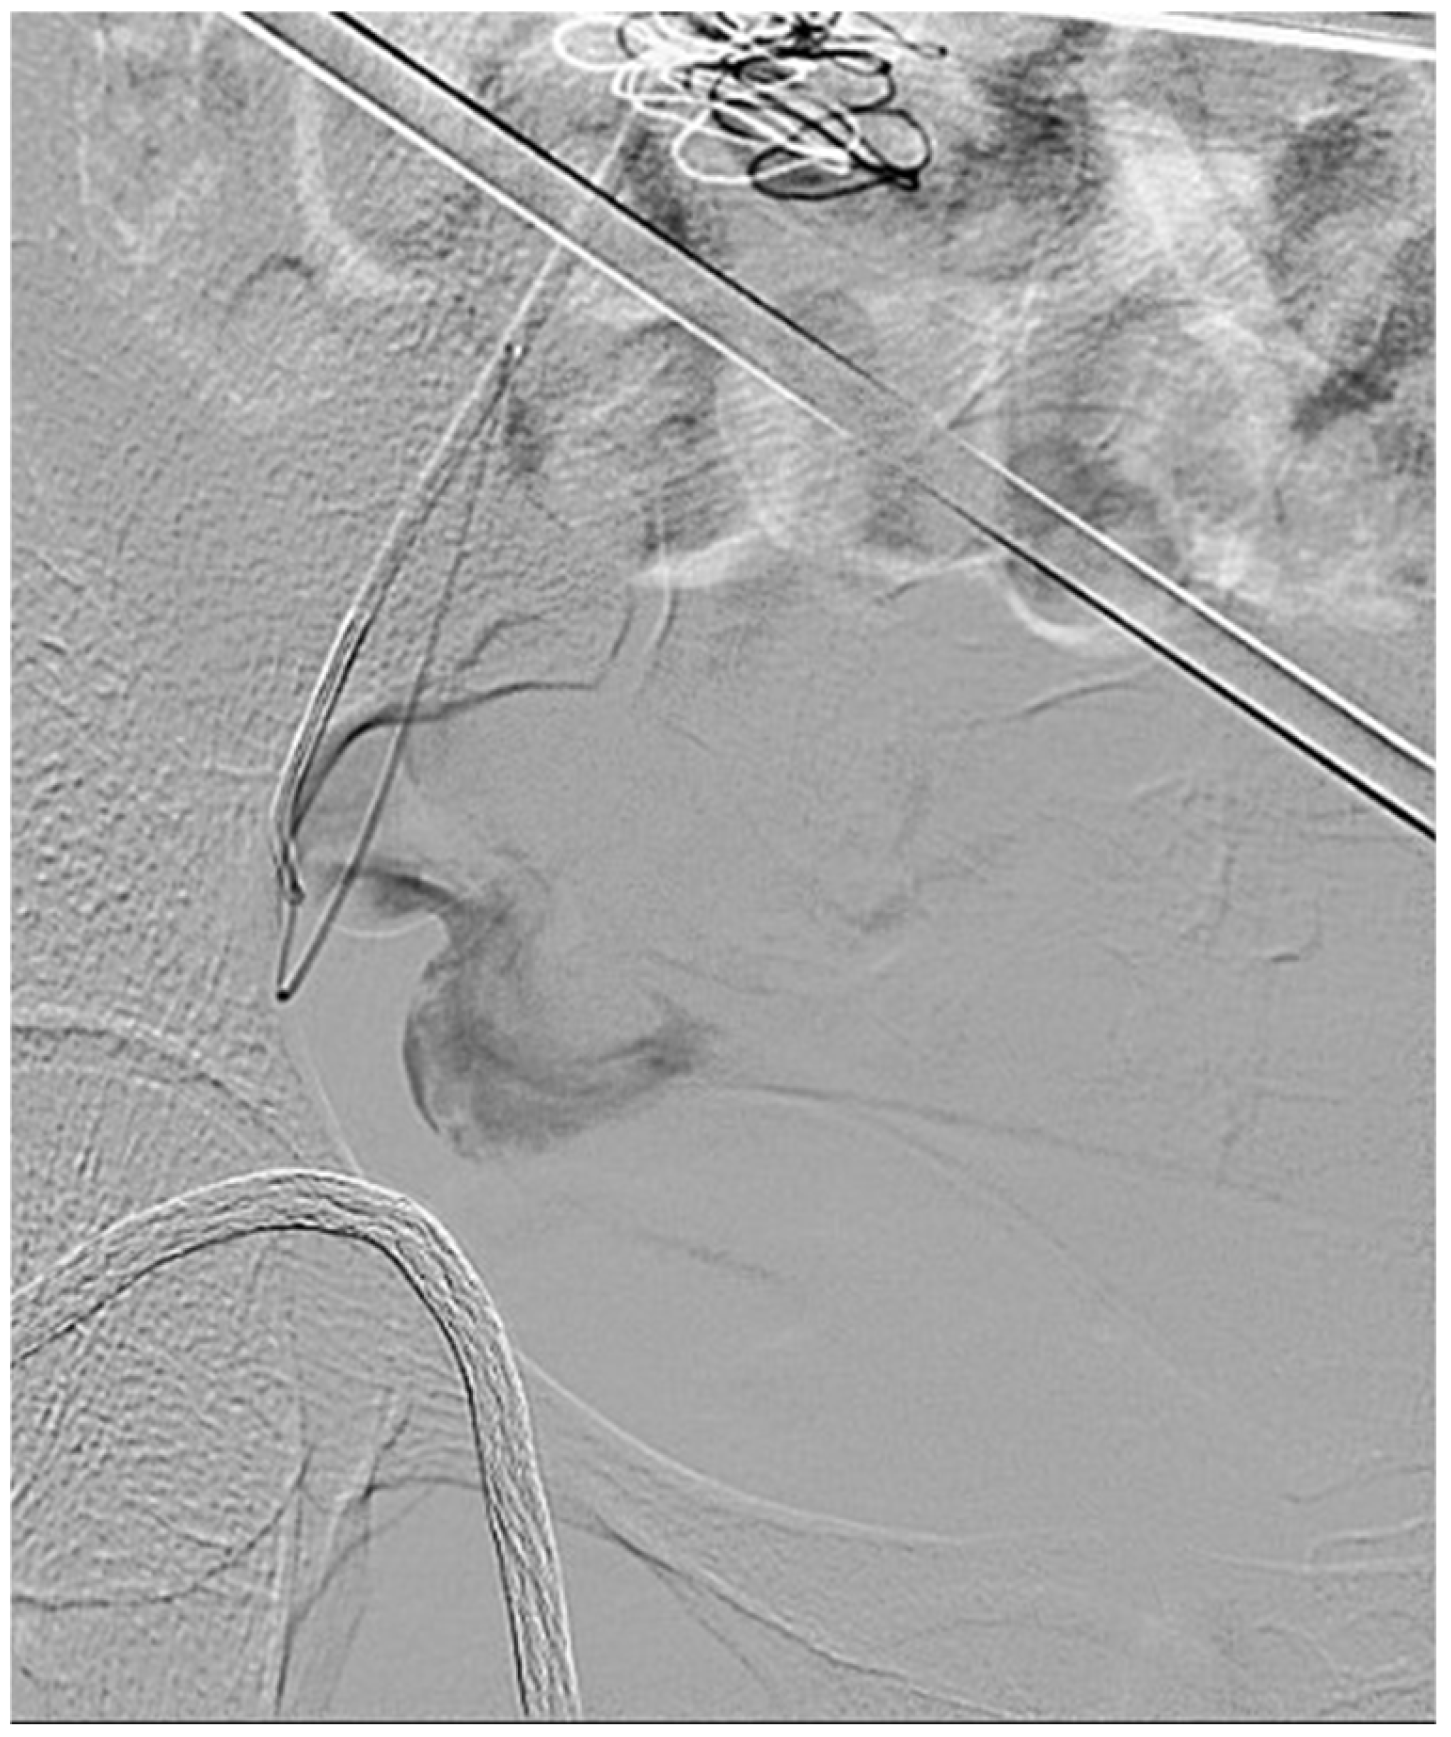

Postoperative complications included skin blistering in one patient, which resolved with conservative management, and cellulitis in another patient, which required a short course of antibiotics. Both patients were discharged home the following day. The third patient experienced a fracture of a large portion of the ice ball intraoperatively, which detached and contacted the bowel. The area was irrigated and suctioned without evidence of bowel injury. The ice ball fracture was also believed to have fractured the ipsilateral inferior epigastric artery, leading to intraoperative bleeding. The bleeding was identified laparoscopically, and manual compression was performed, followed by angioembolization of the inferior epigastric and internal mammary arteries with coils and Gelfoam® (Pfizer, New York, NY, USA) in the hybrid suite (Figure 6). This patient experienced a brief episode of hypotension, which was managed with fluid resuscitation. Hemostasis was confirmed both angiographically and laparoscopically. Because of pain, this patient had an extended postoperative hospital stay of 6 days. Table 2 summarizes the periprocedural details.

Figure 6.

Angiogram shows contrast extravasation from the right inferior epigastric artery in the 3rd patient, which was managed with embolization.

The mean follow-up duration for the first clinic visit was 92 ± 7.1 days. In the first patient, follow-up imaging revealed a 20% reduction in tumor size and a 51.7% reduction in TV, with hypo-enhancement and central necrosis. The second patient’s tumor size remained unchanged (7.6 cm), but there was an 18.7% reduction in TV, with MRI showing hypo-enhancement of the entire tumor. The third patient exhibited a 94.4% increase in tumor size and a 107.8% increase in TV due to hematoma formation following the inferior epigastric artery injury. However, MRI also demonstrated hypo-enhancement in the tumor, a radiologic finding indicative of non-viable tissue and consistent with effective cryoablation. Hence, although the vascular injury led to increases in lesion size due to hemorrhage, it did not necessarily compromise the overall success of the ablation procedure. All the patients experienced complete pain resolution in their follow-up visits, which was subjectively assessed without the use of a pain scale. Follow-up is still ongoing, and long-term outcomes will be reported in the future. Table 3 summarizes the outcomes at follow-up.